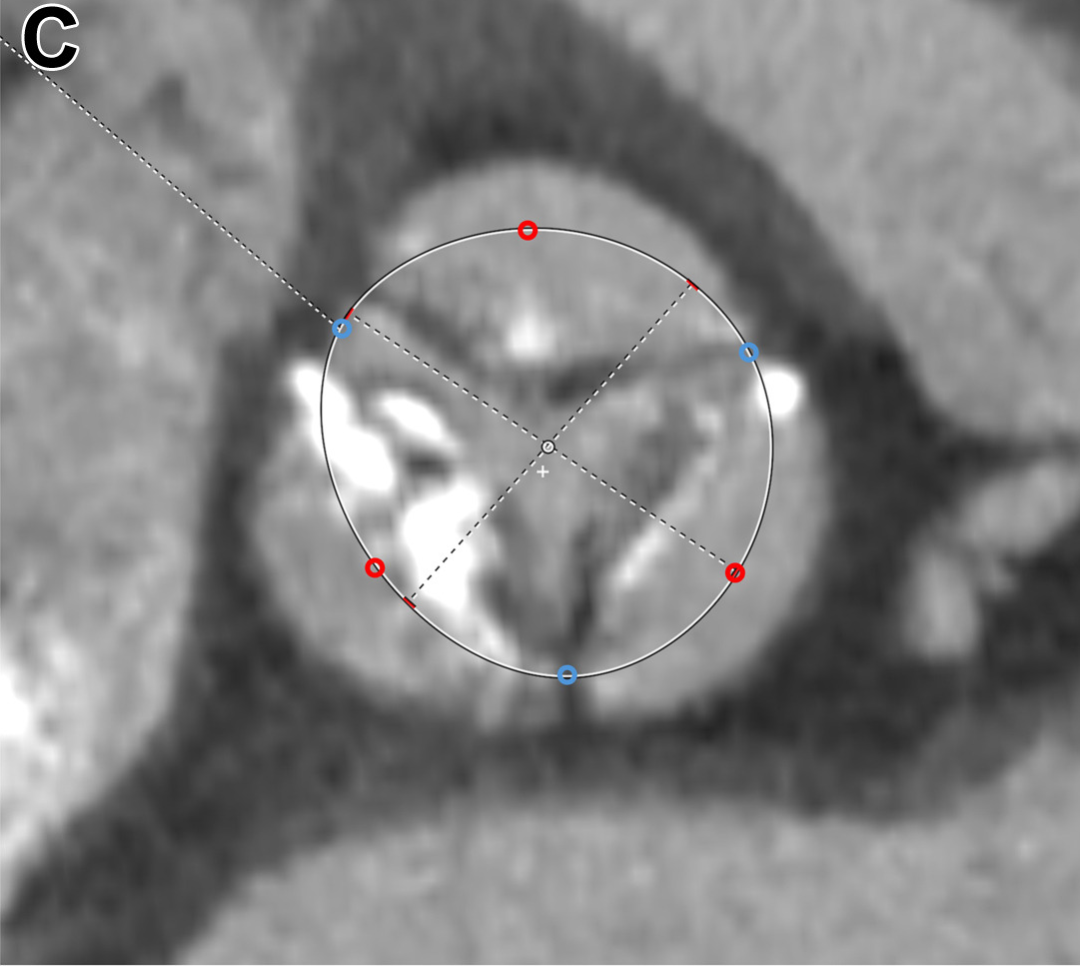

二叶主动脉瓣伴三个窦。蓝色圆点表示置于连合点的初始定位点,左上角蓝色圆点特别标示为置于瓣叶融合嵴的内侧边缘。红色圆点表示置于瓣叶游离缘的点,根据需要向外调整。

三叶主动脉瓣。蓝色圆点表示置于交界的初始定位点。红色圆点表示置于瓣叶游离缘的点,这些点根据瓣叶钙化程度或钙化瓣叶内侧边界的位置向外调整。左下角的红色圆点特别表示当钙化瓣叶受压贴靠主动脉窦壁(sinus wall)时其内侧边缘的位置。

针对不同的主动脉瓣形态,测量时的定位细节有所区别:对于三叶瓣以及具有三个主动脉窦的二叶瓣,首先在影像上标定3个瓣叶交界点,然后在每个瓣叶的游离缘处各添加1个次要标记点;对于只有两个主动脉窦的二叶瓣,则先标定2个交界点,再在两瓣叶的中点各添加1个次要点。根据瓣叶钙化的程度,这些次要定位点可适当向瓣周缘方向调整位置,以模拟瓣膜展开时瓣叶钙化可能被挤压推移的效果,从而更真实地反映植入后瓣膜可能达到的最大扩张范围。最终,通过比较多个平面测量所得的周长,取其中最小的周长值来确定人工瓣膜的尺寸。